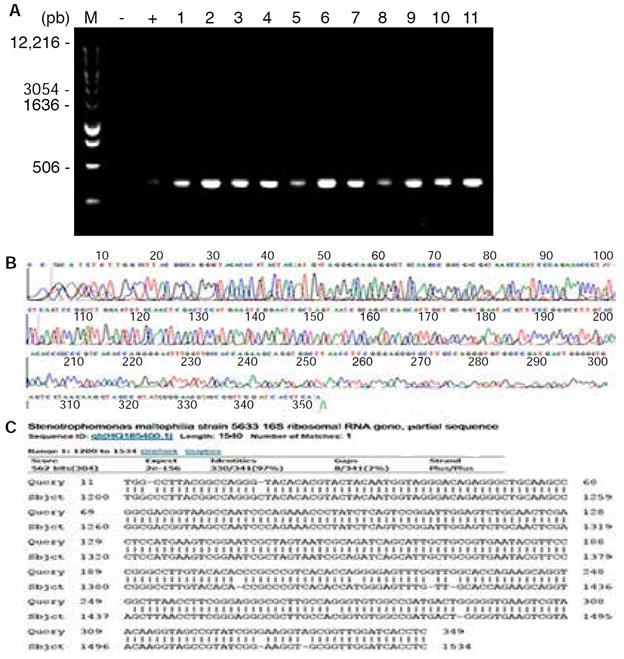

La extracción de ADN se realizó utilizando un kit comercial (DNeasy Blood and Tissue Kit, Qiagen®). La concentración y la pureza del ADN fueron determinadas con el espectrofotómetro NanoDrop 1000 (Thermo Scientific). La evaluación de la integridad del ADN se realizó con la amplificación del gen p-globina. La amplificación de la ADNr 16S se llevó a cabo utilizando los cebadores universales DG74: 5' AGGAGGT-GATCCAACCGCA3' y RW01 5' AACTGGAGGAA-GGTGGGGAT3',13 en un volumen final de 25 ¿vL que contenía 5 ¿vL de ADN (aproximadamente a 50 ng/i/L), 0.5 U de Taq polimerasa (Invitrogen), 1 mM de cada cebador, 3.75 mM de MgCl2, 0.2 mM de cada dNTP y buffer de Taq polimerasa. La amplificación se llevó a cabo en un termociclador Amp PCR System 9700 (Applied Biosystems) usando las siguientes condicio nes de reacción: una desnaturalización inicial de 5 min a 94 oC, seguida de 30 ciclos de desnaturalización a 94 oC por 30 s, alineamiento a 62 oC por 30 s y extensión a 72 oC por 30 s. Finalmente, se llevó a cabo una extensión a 72 oC por 5 min. Se utilizó como control positivo de bacteria el ADN de Helicobacter pylori (ATCC 43504). Los amplicones se purificaron usando ExoSAP-IT (USB) y se secuenciaron con un secuenciador automático ABI PRISM 3130 (Applied Biosystems) usando el kit de secuencia ABI PRISM BigDye Terminator v3.1 (Applied Biosystems). Las secuencias fueron comparadas usando la aplicación del BLAST de la base de datos GenBank http://www.ncbi.nlm.nih.gov/blast/Blast.cgi.

Los datos moleculares permitieron identificar bacterias con identidad alta (mayor del 80%) en las muestras analizadas como se observa en la Figura 2 .

Figura 2. Resultados moleculares representativos. A) Gel de agarosa al 2%, M representa el marcador de tamaño molecular 1 Kb, (-) blanco de reactivos, (+) control positivo de H. pylori (ATCC 43504) y 1-11 muestras representativas de pacientes con periodontitis. B) Electroferograma de secuenciación. C) Identidad reportada en NCBI/ BLAST Assembled Genomes del 97% para S. maltophilia.